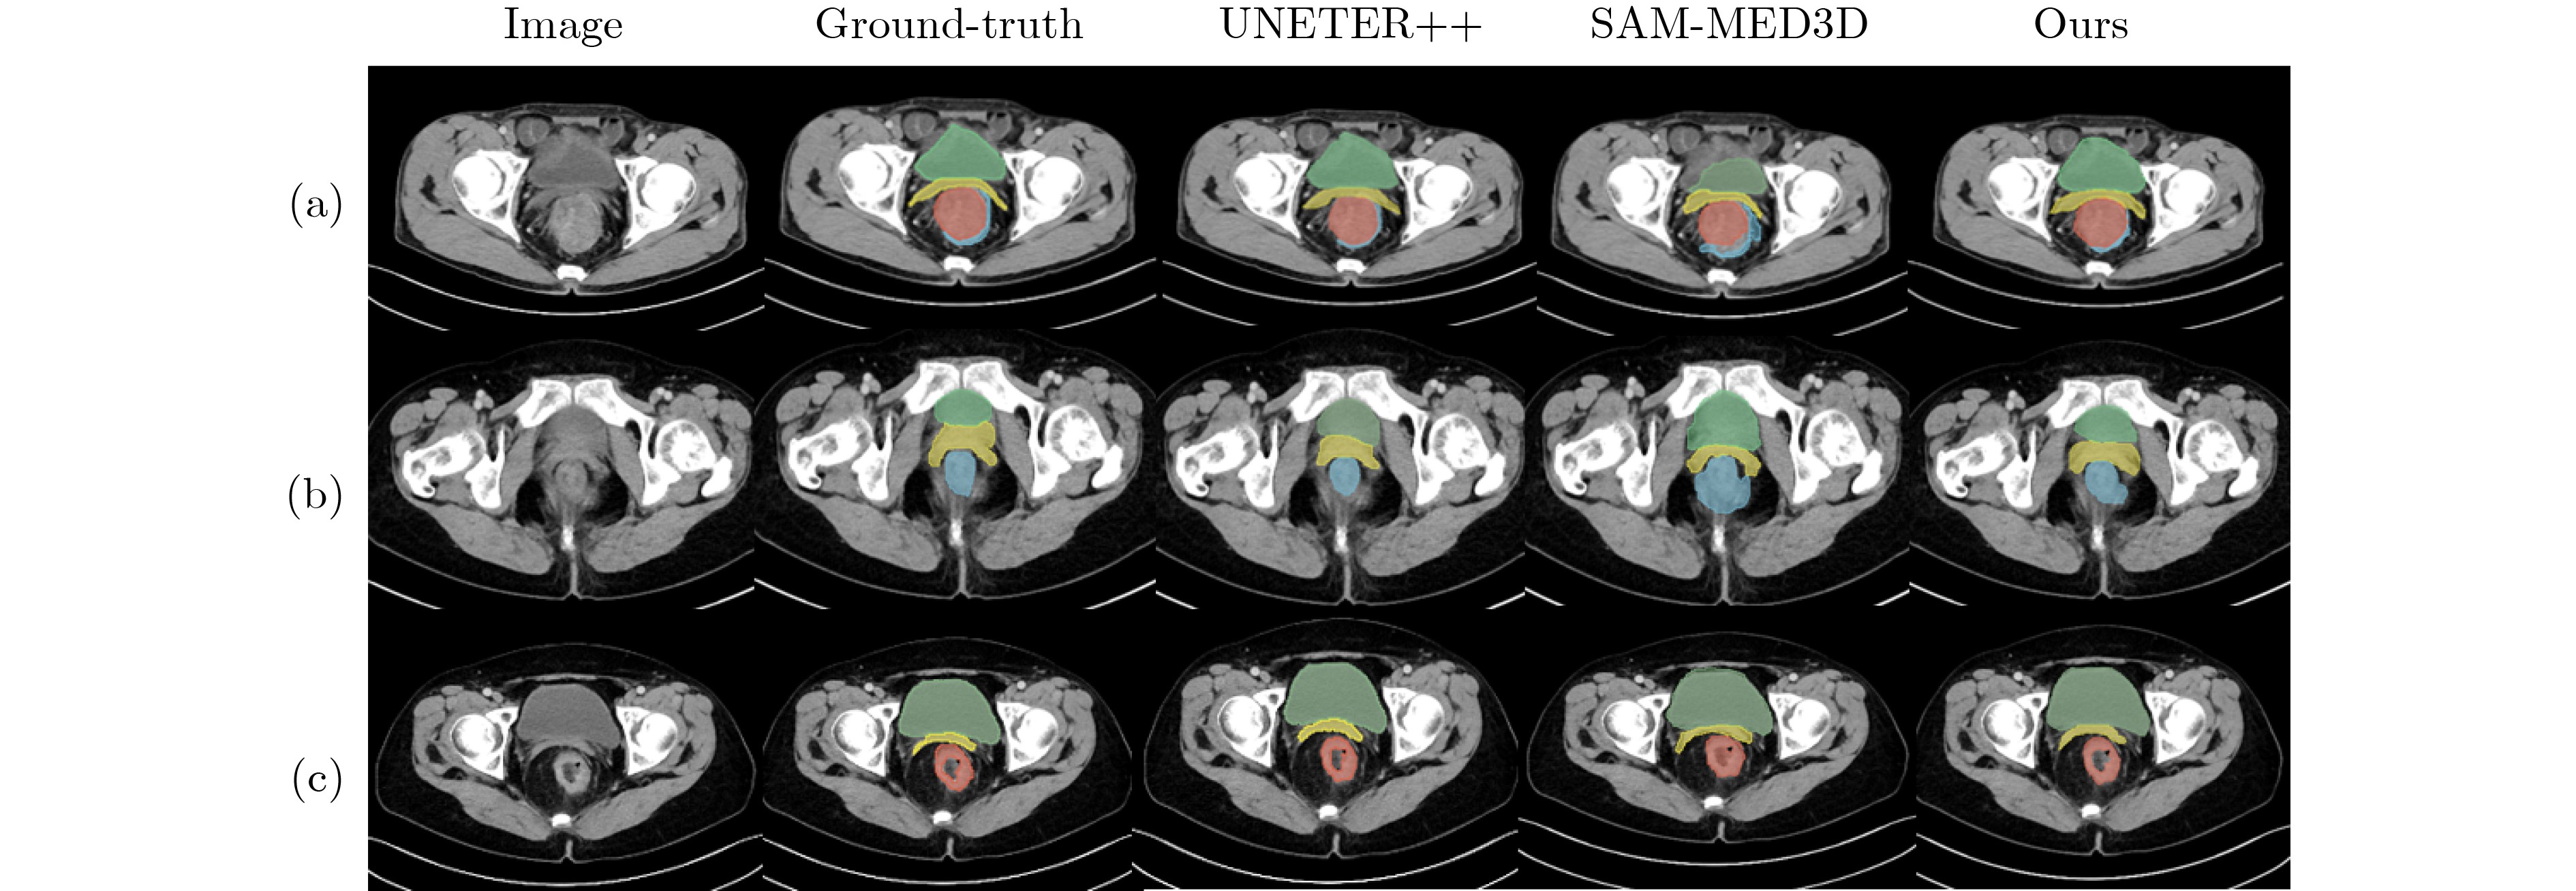

Objective Three-dimensional medical image segmentation is a central task in medical image analysis. Compared with two-dimensional imaging, it captures organ and lesion morphology more completely and provides detailed structural information, supporting early disease screening, personalized surgical planning, and treatment assessment. With advances in artificial intelligence, three-dimensional segmentation is viewed as a key technique for diagnostic support, precision therapy, and intraoperative navigation. However, methods such as SwinUNETR-v2 and UNETR++ depend on extensive voxel-level annotations, which create high annotation costs and restrict clinical use. High-quality segmentation also often requires multi-view projections to recover full volumetric information, increasing radiation exposure and patient burden. Segmentation under sparse radiation measurements is therefore an important challenge. Neural Attenuation Fields (NAF) have recently been introduced for low-dose reconstruction by recovering linear attenuation coefficient fields from sparse views, yet their suitability for three-dimensional segmentation remains insufficiently examined. To address this limitation, a unified framework termed NA-SAM3D is proposed, integrating NAF-based reconstruction with interactive segmentation to enable unsupervised three-dimensional segmentation under sparse-view conditions, reduce annotation dependence, and improve boundary perception. Methods The framework is designed in two stages. In the first stage, sparse-view reconstruction is performed with NAF to generate a continuous three-dimensional attenuation coefficient tensor from sparse X-ray projections. Ray sampling and positional encoding are applied to arbitrary three-dimensional points, and the encoded features are forwarded to a Multi-Layer Perceptron (MLP) to predict linear attenuation coefficients that serve as input for segmentation. In the second stage, interactive segmentation is performed. A three-dimensional image encoder extracts high-dimensional features from the attenuation coefficient tensor, and clinician-provided point prompts specify regions of interest. These prompts are embedded into semantic features by an interactive user module and fused with image features to guide the mask decoder in producing initial masks. Because point prompts provide only local positional cues, boundary ambiguity and mask expansion may occur. To address these issues, a Density-Guided Module (DGM) is introduced at the decoder output stage. NAF-derived attenuation coefficients are transformed into a density-aware attention map, which is fused with the initial masks to strengthen tissue-boundary perception and improve segmentation accuracy in complex anatomical regions. Results and Discussions NA-SAM3D is evaluated on a self-constructed colorectal cancer dataset comprising 299 patient cases (collected in collaboration with Nanjing Hospital of Traditional Chinese Medicine) and on two public benchmarks: the Lung CT Segmentation Challenge (LCTSC) and the Liver Tumor Segmentation Challenge (LiTS). The results show that NA-SAM3D achieves overall better performance than mainstream unsupervised three-dimensional segmentation methods based on full radiation observation (SAM-MED series) and reaches accuracy comparable to, or in some cases higher than, the fully supervised SwinUNETR-v2. Compared with SAM-MED3D, NA-SAM3D increases the Dice on the LCTSC dataset by more than 3%, while HD95 and ASD decrease by 5.29 mm and 1.32 mm, respectively, indicating improved boundary localization and surface consistency. Compared with the sparse-field-based method SA3D, NA-SAM3D achieves higher Dice scores on all three datasets ( Table 1 ). Compared with the fully supervised SwinUNETR-v2, NA-SAM3D reduces HD95 by 1.28 mm, and the average Dice is only 0.3% lower. Compared with SA3D, NA-SAM3D increases the average Dice by about 6.6% and reduces HD95 by about 11 mm, further confirming its capacity to restore structural details and boundary information under sparse-view conditions (Table 2 ). Although the overall performance remains slightly lower than that of the fully supervised UNETR++ model, NA-SAM3D still shows strong competitiveness and good generalization under label-free inference. Qualitative analysis shows that in complex pelvic and intestinal regions, NA-SAM3D produces clearer boundaries and higher contour consistency (Fig. 3 ). On public datasets, segmentation of the lung and liver also shows superior boundary localization and contour integrity (Fig. 4 ). Three-dimensional visualization further confirms that in colorectal, lung, and liver regions, NA-SAM3D achieves stronger structural continuity and boundary preservation than SAM-MED2D and SAM-MED3D (Fig. 5 ). The DGM further enhances boundary sensitivity, increasing Dice and mIoU by 1.20% and 3.31% on the self-constructed dataset, and by 4.49 and 2.39 percentage points on the LiTS dataset (Fig. 6 ).Conclusions An unsupervised three-dimensional medical image segmentation framework, NA-SAM3D, is presented, integrating NAF-based reconstruction with interactive segmentation to achieve high-precision segmentation under sparse radiation measurements. The DGM effectively uses attenuation coefficient priors to enhance boundary recognition in complex lesion regions. Experimental results show that the framework approaches the performance of fully supervised methods under unsupervised inference and yields an average Dice improvement of 2.0%, indicating strong practical value and clinical potential for low-dose imaging and complex anatomical segmentation. Future work will refine the model for additional anatomical regions and assess its practical use in preoperative planning. -